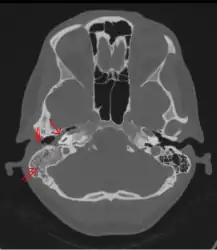

The diagnosis of mastoiditis is clinical—based on the medical history and physical examination. Imaging studies provide additional information; The standard method of diagnosis is via MRI scan although a CT scan is a common alternative as it gives a clearer and more useful image to see how close the damage may have gotten to the brain and facial nerves. Planar (2-D) X-rays are not as useful. If there is drainage, it is often sent for culture, although this will often be negative if the patient has begun taking antibiotics. Exploratory surgery is often used as a last resort method of diagnosis to see the mastoid and surrounding areas.[7][8]

Acute mastoiditis -

CT scan: Otitis media (simple arrow) and mastoiditis (double arrow) of the right side (left side in image). The external auditory canal is partially occupied by suppuration (triple arrow). 44-year-old woman